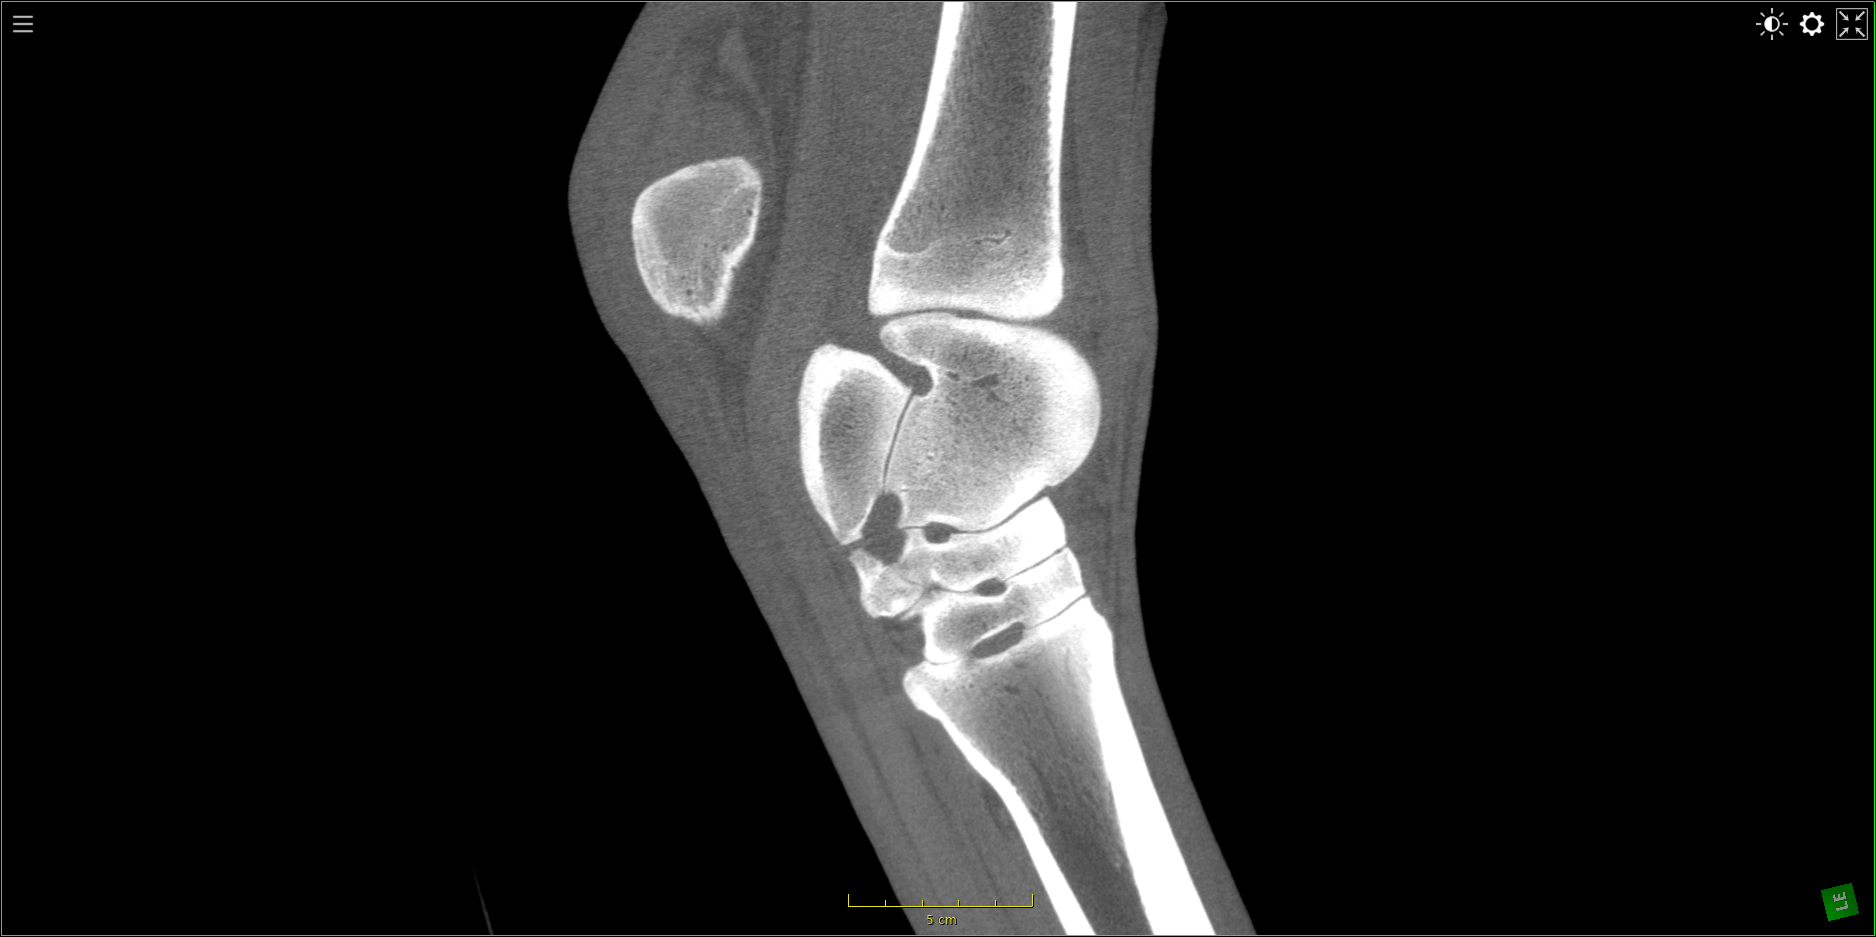

Our High Definition Volumetric Imaging (HDVI) technology represents the most advanced stage of Flat Panel CT technology. It offers exceptional diagnostic imaging for both hard and soft tissues, in diagnostic settings and intraoperative theaters. It is the gold standard for orthopedic applications.

High Definition Volumetric Imaging (HDVI) Computed Tomography and Fluoroscopy in one device.

Diagnostic and intraoperative use

Diagnostics, preoperative, intraoperative and post-operative environments: our technology offers full capabilities.